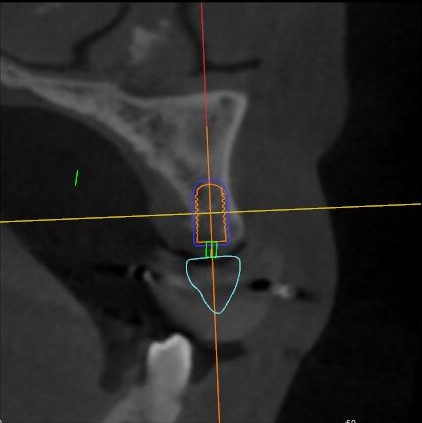

矢狀面視圖

根據(jù)患者CT顯示,使用種植導(dǎo)航軟件設(shè)術(shù)前手術(shù)方案??紤]到患者拒絕手術(shù)摘除上頜竇囊腫等因素,此次手術(shù)選用了Straumann骨水平4.10*8.0mm的植體,植體末端位點(diǎn)設(shè)計(jì)距上頜竇底壁2mm處的同時(shí)兼顧種植方向和修復(fù)間隙,來(lái)達(dá)到理想的效果。